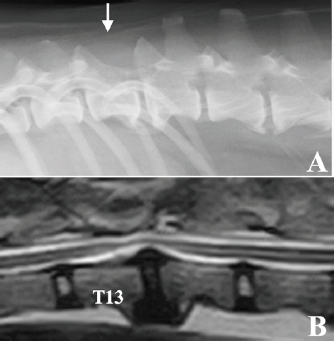

An 18-month-old spayed female crossbreed dog presented with progressive hindlimb paralysis over the previous months. She could not stand or walk unaided at her first visit and showed severe pain upon palpation of the thoracolumbar spine. Plain spinal radiography and routine blood tests were normal. Computed tomography of the thoracolumbar spine showed a clear contrast-enhanced mass lesion of the spinal cord at T13, suggesting the presence of spinal tumors; however, the detailed relationship between the tumor tissue and the normal spinal cord was unknown (Fig. 1). Six days later, the dog underwent surgical removal of the presumed tumor under general anesthesia, as the animal’s owner wanted aggressive treatment, including surgery.

Fig. 1. Computed tomographic findings at T13 of the case. (A) Without contrast medium, (B) with an intravenous administration of contrast medium. A clear contrast-enhanced mass lesion of the spinal cord could be observed in the contrast study (B, arrow head).

After treatment, the dog lived for approximately 10 years with mild proprioceptive deficits in the left hind limb. No tumor recurrence was observed on periodic follow-up magnetic resonance imaging (MRI) examinations carried out 10 and 21 months after surgery. Nine years after surgery, the dog returned to the hospital to evaluate the thoracolumbar spinal cord due to the gradual development of hindlimb weakness. Plain radiography of the thoracolumbar spine showed spondylosis deformans between T13–L1 and L2–3, with the former being consistent with the surgical site (Fig. 3A). MRI examination showed no recurrent tumor tissue in the thoracolumbar spinal cord; however, there was slight compression of the spinal cord from the ventral side at T13–L1 (Fig. 3B). This was thought to be due to the proliferation of bony tissues associated with intervertebral instability after laminectomy. The dog died 11 years after surgery for reasons unrelated to the tumor. According to the owner, the dog had vomiting of unknown cause for several months and died of aspiration pneumonia. No necropsy was performed.

Fig. 3. Radiographic and MRI findings of the thoracolumbar spine of the case 9 years after surgery. (A) Radiographic features of spondylosis deformans were observed in both T13–L1 and L2–3. The spinous process of T13 was missing due to laminectomy (white arrow). (B) MRI (T2-weighted image) showed that the spinal cord was slightly compressed from the ventral side in T13–L1, probably due to the proliferation of bone tissue due to spinal instability. No tumor tissue was observed in the spinal cord.